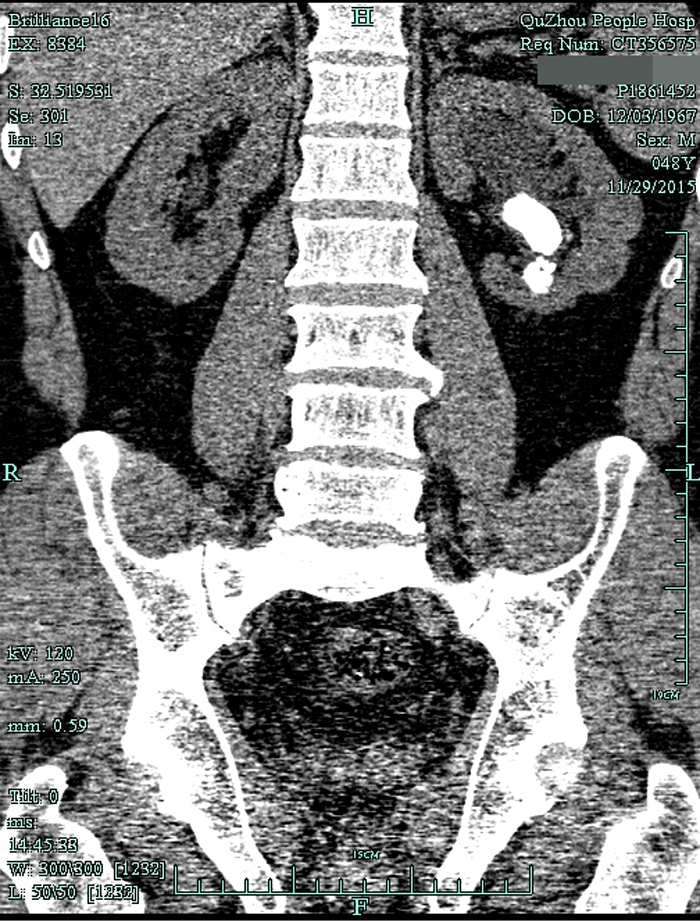

術(shù)前CT1

術(shù)前CT2

??? 一查泌尿系CT,兄弟倆都是左腎鹿角型結(jié)石,而且已經(jīng)有腎積水。根據(jù)CT檢查結(jié)果以及結(jié)石體積大(3cm)、質(zhì)地硬的特點(diǎn),萬(wàn)醫(yī)師建議兩人行經(jīng)皮腎鏡碎石取石術(shù),才能將結(jié)石清理干凈。